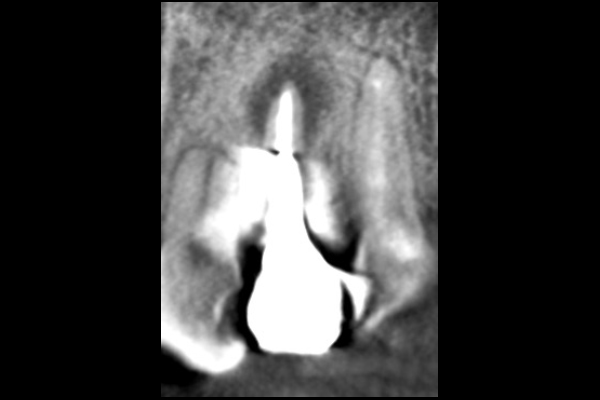

30代女性の前歯部の症例

- 主訴

- 「前歯で咬むと違和感がある」とのことでご来院されました。数週間前から症状があり、他の医院では「抜歯の可能性がある」と言われ、不安に感じていらっしゃいました。

- 期間

- 治療期間2ヶ月、治療回数3回、レントゲン写真で治癒を確認できるまでの期間6ヶ月

- 治療内容

- 1.古い被せ物の除去と虫歯の徹底除去

まず、古い銀歯を外し、内部に広がっていた虫歯を丁寧に取り除きました。

2.マイクロスコープ下での根管治療

唾液などによる細菌の侵入を防ぐ「ラバーダム」を装着し、マイクロスコープ(歯科用顕微鏡)で根管内を数十倍に拡大しながら治療を進めました。複雑な形状の根管の内部まで、汚染された組織を徹底的に洗浄・消毒します。

3.根管充填(こんかんじゅうてん)

根管内が完全にクリーンになったことを確認し、再感染を防ぐために専用の薬剤で隙間なく密閉しました。

4.土台と被せ物の作製

歯の強度を補うための土台を立て、最終的なセラミックの被せ物を作製し、装着しました。